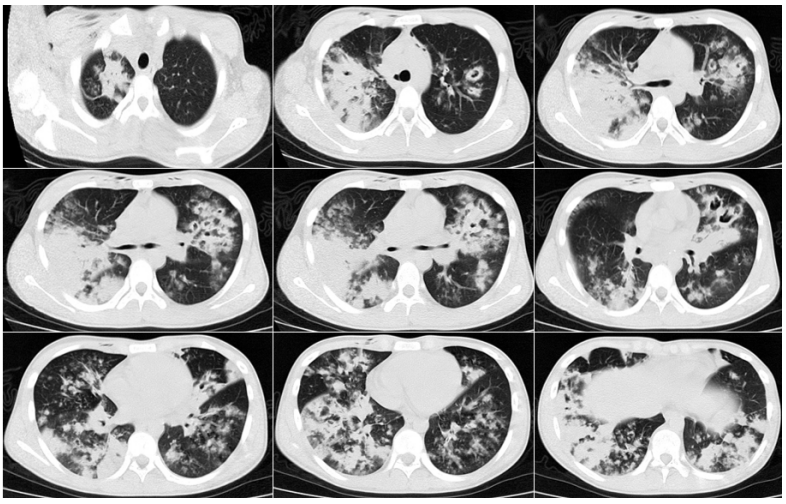

糖皮质激素的使用在其他病种中也被认为是IPA的危险因素,在重症流感中也不例外,有研究表明入ICU前系统性应用大剂量糖皮质激素是继发IAA的独立危险因素。除了重症流感,患者可能还会合并其他基础疾病,尤其是可以影响患者免疫状态的基础疾病,可能也是IAPA的危险因素。病例1::男,15岁,学生;主因“发热、干咳16天,加重伴呼吸困难8天”入院。既往体健,无基础病。入中日医院MICU时间为2018年1月16日,死亡时间为2018年1月26日。患者16天前(2017年12月30日)出现发热,体温39.0℃,伴干咳、咽痛。8天前(2018年1月7日)出现呼吸困难。血气分析示Ⅱ型呼吸衰竭,WBC 24.1×109/L,NE% 90%,PCT 3.3 ng/ml。不断升级抗细菌治疗,效果不佳:头孢曲松→亚胺培南、阿奇霉素、利奈唑胺。7天前(2018年1月8日)确诊乙流,加用帕拉米韦+奥司他韦。2天前(2018年1月13日):血GM试验测值增高,痰培养烟曲霉,诊断IAPA,加用伏立康唑。2018年1月15日转入中日医院呼吸与危重症医学科MICU。2018年1月8日胸部CT(起病1周余)提示气压伤非常严重,以及沿气道分布的斑片和小结节。此时的影像学提示曲霉感染已经显而易见(图1),但尚未得到病原学证据的支持,因此外院当时并未予抗真菌治疗,延迟抗真菌治疗也是导致患者预后不良的重要原因之一。1月15日(转入中日医院MICU后)气管镜检查,镜下可见气道狭窄和黏膜充血水肿均较明显,表面大量白苔,触之易出血(图2)。此时除了曲霉感染,BALF病原学还发现合并了CRAB感染。患者影像学快速进展,1月15日胸部CT显示双肺弥漫性沿支气管血管束分布的结节影、斑片影、厚壁空洞及片状实变(图3)。1月22日胸部CT显示双肺病变明显进展,结节、斑片融合为大面积实变影(图4)。最终患者因CRAB血流感染导致感染性休克,后期又并发脓毒性心肌病,最终去世。病例2::女,65岁,退休。间断干咳伴发热10天,加重伴呼吸困难4天。既往2型糖尿病史35年,使用精蛋白生物合成人胰岛素注射液(预混30R)治疗,血糖波动在7~8 mmol/L。患者入ICU时间为2018年2月4日,出ICU时间为2018年4月19日。10天前(2018年1月25日)“感冒”后出现干咳,伴发热,体温最高37.8℃。7天前(2018年1月28日),血常规:WBC 12.49×109/L,NEU% 87.5%,LYM% 7%,予莫西沙星。1月30日复查血常规:WBC 23.88×109/L,NEU% 91.5%,LY% 4.6%,调整抗生素为头孢噻肟+莫西沙星。4天前(1月31日)呼吸困难加重,SpO2(未吸氧)88%,复查血常规:WBC 37.04×109/L,NEU% 93.7%,LYM% 1.7%,PCT 1.79 ng/ml,痰涂片可见真菌孢子及菌丝。3天前(2月1日)咳痰费力,SpO2降至71%,开放气道吸痰过程中心率降至32次/min,立即心肺复苏,气管插管球囊辅助通气,约12 min患者自主心率恢复,接呼吸机辅助呼吸,经气道可吸出大量黄色黏痰,痰流感病毒核酸阳性。1月31日胸部CT示:沿支气管血管束分布的斑片和实变影(图5)。气管镜下可见充血、水肿,曲霉特征性假膜相对较少(图6)。

2月13日复查胸部CT(抗真菌治疗14天)显示影像学较前好转(图7)。患者病程中也经历了院感、肺外脏器支持等,病情最终好转出院。(1)一般情况:流感合并曲霉感染患者, 男性居多, 年龄大, 基础病情更加严重, 伴有免疫抑制因素(例如: 肿瘤、免疫抑制剂、激素)。(2)起病时间较早(入ICU早期),入ICU至IAPA诊断的平均时间<72小时(3天),短于COVID-19相关肺曲霉病(CAPA)4~13天,流感至IAPA诊断时间为(13±7)天。(3)临床症状/体征不典型:IAPA的临床表现无特异性,可表现为发热、咳嗽、呼吸困难、病情加重且对现有治疗无效。部分患者可能出现咳黑褐色痰或咯血,并且有致死性大咯血风险。CAPA和COVID-19相关肺毛霉病(CAPM)患者发展为重症需入住ICU的比例更高。此外,患者常合并呼吸衰竭/ARDS、急性肾损伤(AKI)、感染性休克。(4)实验室及影像学检查:实验室检查有一项比较重要的提示,IAPA患者可能会因为炎症反应强烈而导致WBC非常高,但PCT一般不会明显升高,淋巴细胞常明显降低。影像学表现有其特点(如前所述)。(5)独立危险因素:ICU早期WBC明显增高(>10×109/L)、入ICU后应用激素、CT特征表现(多发结节、空洞)是IAPA的独立危险因素。但仍需大样本量、多中心的病例对照研究进一步验证。从上述两个病例可以发现,由于患者的症状、体征、实验室检查大部分不特异,且常被伴发的流感及混合的细菌感染所掩盖,因此IAPA的早期诊断较困难。微生物学依据是诊断IAPA的金标准,而在拿到微生物学证据之前,影像学和气管镜检查可以帮助我们寻找蛛丝马迹,在临床上具有重要意义及提示作用,有助于早期诊断。因此,熟悉其表现尤为重要。(1)微生物学证据:2020年欧洲医学真菌学协会/国际人类和动物真菌学学会(ECMM/ISHAM)发布的关于CAPA的定义及共识声明中提到的检测方法以及cut off值可供参考,包括:①BALF直接镜检阳性、BALF培养/PCR阳性,血GM/LFA>0.5,BALF-GM/LFA≥1;②血浆/血清/全血PCR阳性≥2次;③单次BALF PCR阳性且CT<36;④单次血浆/血清/全血PCR阳性,且单次BALF-PCR阳性(不要求CT值)。(2)CT表现:CT在IAPA的早期诊断中具有重要的提示意义。病变沿支气管血管束分布;合并曲霉感染患者有明显的气道受累,包括气道壁增厚、气道狭窄,以及树芽征;典型的病变性质是结节和斑片,空洞及新月征不多见,但有特异性;大片实变影也相对特异,且提示预后差。(3)气管镜下表现:气管镜也是一种非常重要的早期诊断IAPA的手段,可以发现气管镜下典型的假膜。除了观察气道病变的特点及范围,还可以获得高质量的下呼吸道标本,有助于提高真菌培养阳性率,获取及动态监测BALF-GM试验结果。此外,气管镜还能够进行痰液引流。对于气道病变非常严重或局限的患者,气管镜还可以进行气道内给药。值得一提的是,来自欧洲7个国家和美国以及中国台湾等地的29名专家提出了IAPA诊断专家共识,2023年已发表在Intensive Care Medicine 杂志上,将IAPA分为曲霉菌性气管支气管炎及侵袭性肺曲霉病,高度强调了气管镜的重要性,无论是气管镜镜下表现还是气管镜获取BALF标本进行GM试验或真菌培养都是共识中的重要条目,可能有助于IAA的早期诊断。